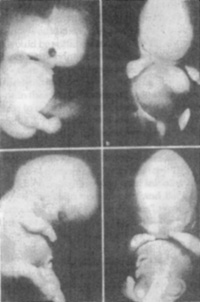

from the natural world. Rudolf Steiner's answer was that medicines from the different elemental worlds act on different aspects of the essential human being. In this respect, animal-based medicines act on the ether body.(24) In the special case of organ preparations deriving from higher vertebrates, there is also another point of view. If we compare the embryos of those vertebrates with human embryos, the morphology shows considerable agreement. Figures 4 and 5 show approximately comparable developmental stages of fox and human embryos. We note that animals go through a stage that is close to the human but then move away from this, whereas the human being remains close to his origin in his conformation. This is impressively demonstrated by the embryogenesis of the hand. At one stage, animals (see wild pig embryo. Figures 6 and 7) also show a five-rayed "human hand" with a thumb capable of opposition, but this later becomes an animal extremity with different specialization. We see, therefore, that forces have been active in the animal organ and lie hidden in it that relate to the human being. These form-giving forces originate in the etheric. This explains why such organs can be made into medicines for humans. Direct evidence is presented here that the whole of nature, in its origins, is related to man - something also discovered in the science of the spirit.

Organ-configuring processes are particularly evident in embryogenesis, when specific organs arise from a material basis of undifferentiated cells. The human hand is such an organ (tool) par excellence. An undifferentiated

brachial bud develops in the 4th week. Finger rays become visible in the 7th week, and the previously-formed tissue between them must perish by the 8th week if the hand is to be fully functional (Fig. 2). Just as a sculptor removes material from outside to create his work of art, so the hand emerges as cells die off in a process that goes from the periphery inwards. The cells dissolve in a process called "apoptosis" caused by their own lysosomal enzymes.(5) It is possible to "call on" apoptotic capacities in the case of tumor cells as is evident from the cytotoxic properties of mistletoe given locally in high doses to effect cytolysis.(6)